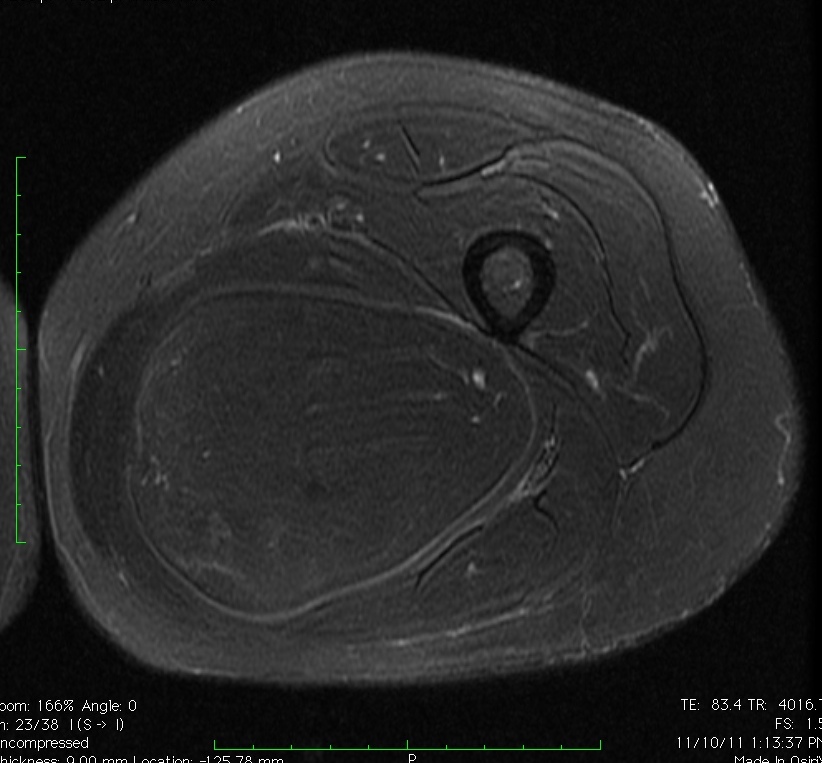

MRI

• Follows the signal characteristics of subcutaneous fat on all sequences

• T1: High Signal

• T2: Intermediate Signal; Low Signal with Fat Suppression

• Minimal or No enhancement with gadolinium

Fig. 1A, 1B, 1C, 2A, 2B, 2C: MRI of a lipoma: T1- weighted images shows an homogeneous mass in the posterior compartment of the thigh with high signal, saturates on fat saturated sequences with no or minimal enhancement. On T2-weighted images demonstrate an intermediate signal on FSE T2, saturates (becomes dark) on fat saturated sequences.